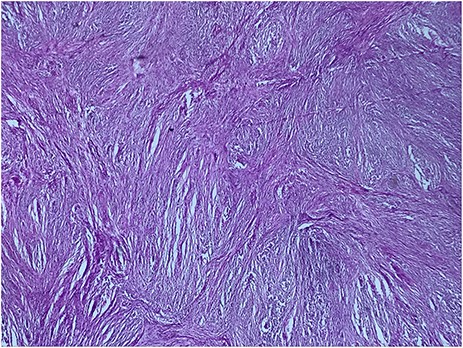

A 73-year-old woman was referred to our general surgery service. Her complain was intermittent gastric discomfort. There was no significant past medical history. There was no history of upper gastrointestinal bleed, or past surgical interventions with no abnormalities found on physical exam. An esophagogastroduodenoscopy (EGD) revealed a submucosal mass in the gastric body. Biopsy of the mass showed no evidence of malignancy. Computerized tomography (CT) scan of the abdomen showed an exophytic solid homogeneous mass along the greater curvature of the stomach and partly projected into the gastric lumen, causing smooth indentation measuring 8 × 8 × 6 cm3 (Fig. 1). The patient’s laboratory results were unremarkable. A presumptive diagnosis of GIST was made. The patient underwent successful wedge resection of the mass through laparotomy and the specimen was sent to pathology. On gross examination, a white intramural, nodular, solid mass measuring 8.7 × 8.8 × 6.7 cm was seen. A cut section revealed whirling trabeculation with a biphasic proliferation of compact hypercellular areas and myxoid hypocellular areas (Fig. 2). Sections from the tumor showed interlacing bundles of spindle cells, which had elongated nuclei, ill-defined cytoplasmic borders and palisading nuclei (Fig. 3). No nuclear atypia was noted. No mitotic activity and no necrosis were identified. There was no lymph node involvement and the surgical margin was negative for tumor cells. A histological diagnosis of a benign mesenchymal tumor was made. Immunohistochemistry (IHC) staining was strongly positive for S-100 (Fig. 4), whereas c-Kit, CD 34; DOG 1; smooth muscle actin (SMA), desmin and AE 1/AE 3 were negative. Hence, a final diagnosis of schwannoma was made. The postoperative period was uneventful and the patient was dismissed from the hospital after 5 days.

The tumor cells are narrow, elongated and wavy with tapered ends interspersed with collagen fibers (HE, G x 400)